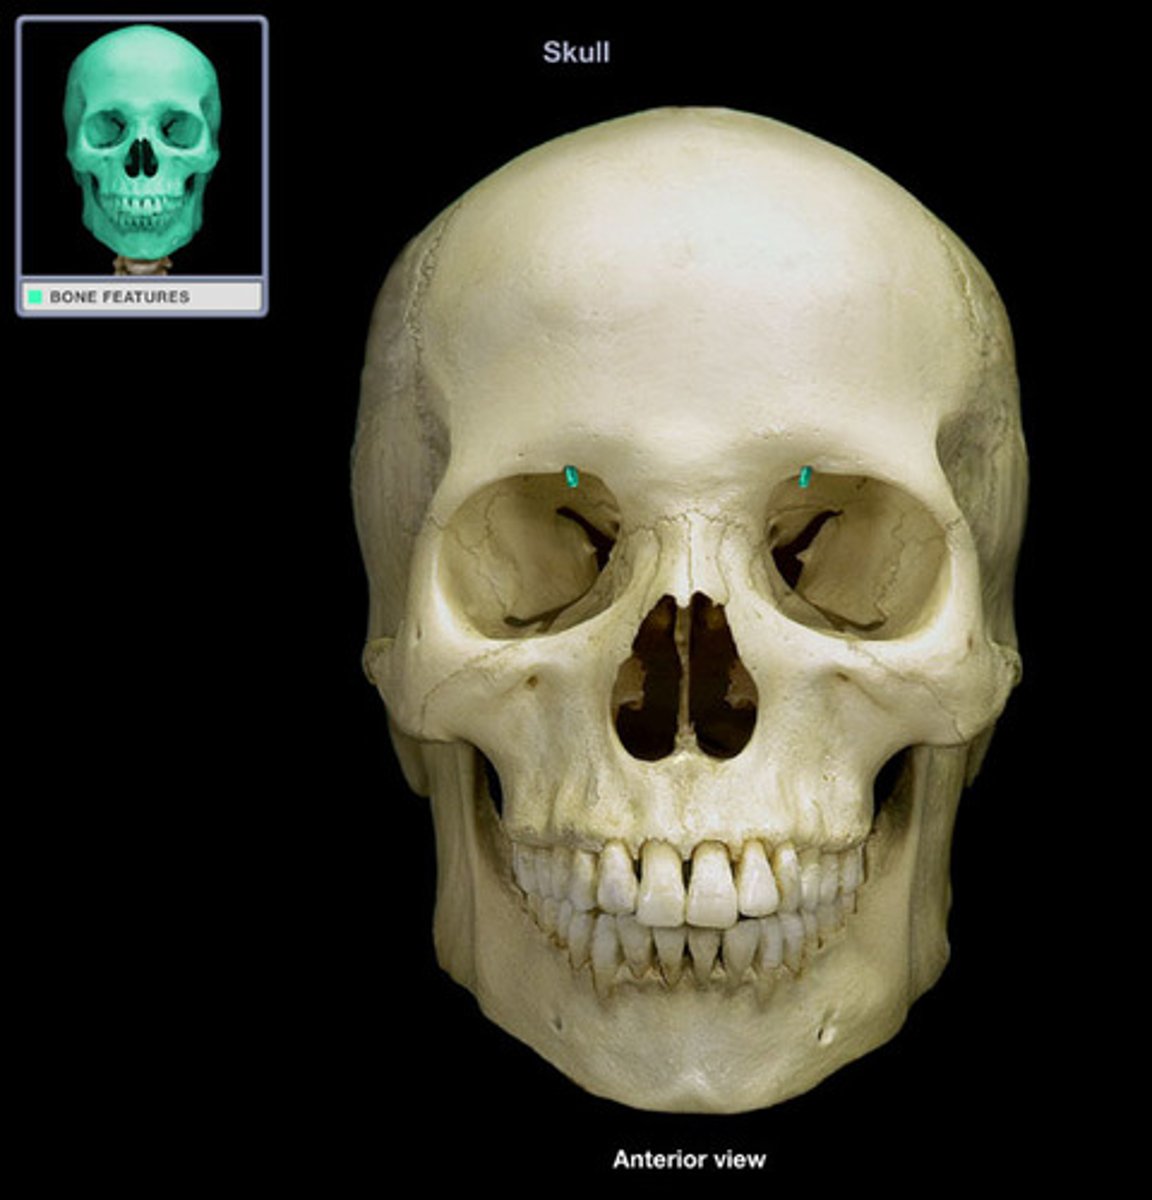

Sagittal suture

Coronal suture

Lambdoid suture

Squamous suture

Zygomatic suture

Supraorbital foramen

Optic canal

Superior orbital fissure

Inferior orbital fissure